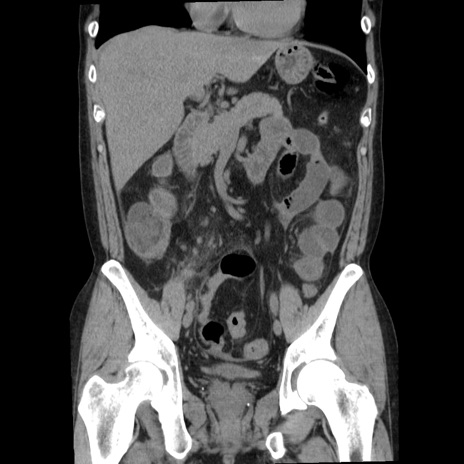

症例29(冠状断像)

【症例】40歳代男性

【現病歴】2日前から胃痛あり。徐々に周期的な激痛に変化した。本日になっても激痛があるため受診。

【身体所見】意識清明、BT 38-39℃台あり、腹部:膨満、やや硬、右下腹部に圧痛あり。

【データ】WBC 8500、CRP 23.26